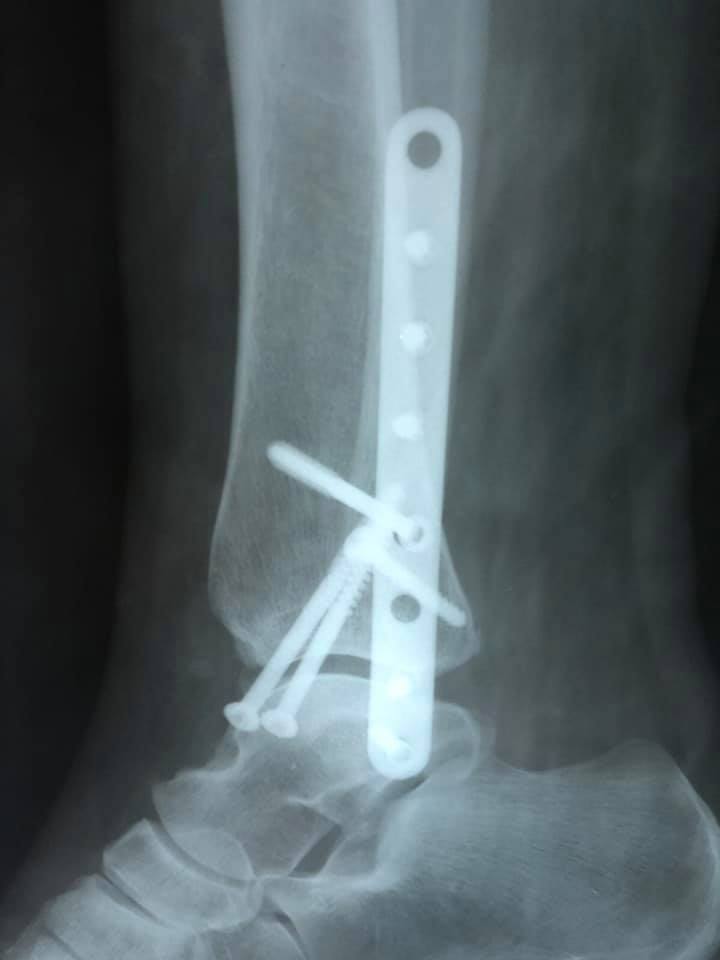

Завдяки вчасному зверненню та професіоналізму лікаря-ортопеда-травматолога, жінку вдалося врятувати. В ургентному порядку жінку доставили в КНП «НЦМЛ». Після огляду лікар встановив діагноз: відламковий перелом кісточок гомілки з вивихом стопи.

Пацієнтці виконали відкриту репозицію уламків з внутрішньою фіксацією. Операція пройшла успішно.